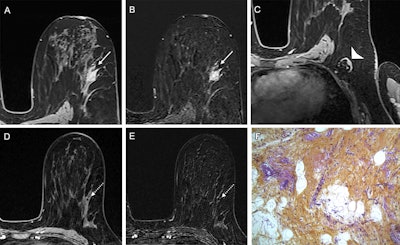

Example of a true-positive radiologic complete response at dynamic contrast-enhanced MRI in a 53-year-old woman who underwent neoadjuvant chemoimmunotherapy for triple-negative breast cancer. (A-C) Axial T1-enhanced dynamic contrast-enhanced MRI scans acquired before treatment. The cancer appeared as a spherical 20-mm mass enhancement in the left breast, indicated by arrows on (A) native and (B) subtracted images. (C) Native image shows the absence of axillary node involvement (arrowhead). (D, E) At post-treatment MRI, no residual enhancement was observed within the initial tumor bed, marked by a coil (dashed arrow), on (D) native and (E) subtraction scans. (F) Pathologic examination after chemoimmunotherapy revealed no residual invasive cancer in the breast or lymph nodes, confirming a pathologic complete response (hematoxylin-eosin stain; magnification, 200×).RSNA